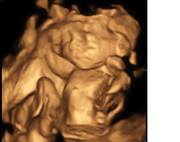

Už se nemůžeme dočkat našeho mrňouska :)) poslední týden se v bříšku pěkně vrtí, včera u paní doktorky se taky pěkně předvedla. Moc pěkně se tam vrtěla až paní doktorka nadávala že se nemůže ani pořádně podívat. Taky na místo 5 fotek pořídila jen jednu.

[336139] nikca: uzasna fotka!!!! Doufam ze pristi tyden si odnesu taky neco podobneho :) Jinak holky co se tyce toho briska ja bych byla radsi kdyby to slo videt, mam nizky tlak a je mi venku furt zle takze sama skoro nikam nechodim, a kdyz uz tak na sebe narvu tehu pas s nozickama nebo rucicka s vedomim ze az to nekdo uvidi tak mu to dojde, ale reknu vam, ze nekteri lide a stalo se mi to s jednou pani, kdyz mi zabylo zle me ani sednout nepustila a volne misto co mela vedle sebe mi rekla ze drzi kolegyni, tak to mi prislo uplne na hlavu. Mozna kdyby to brisko slo videt bylo by to jednodussi, hold ted vsude jen s chlapem, ktery mi to misto vydobije :)